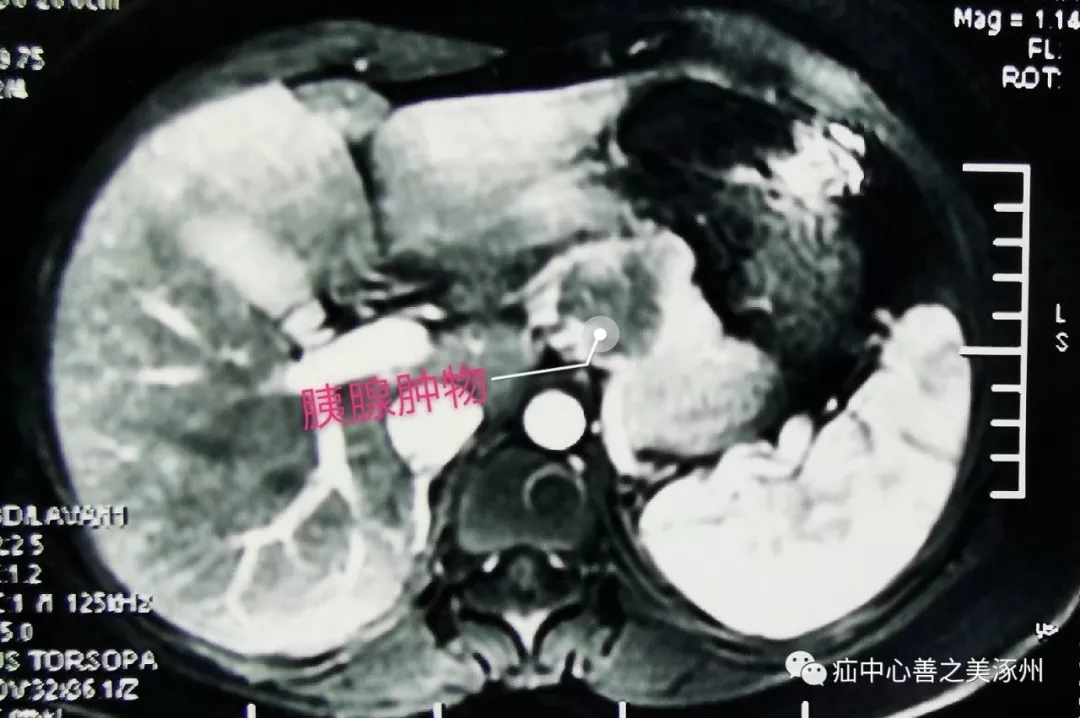

近日,我們普外二科成功為一名胰腺腫物患者行“全腹腔鏡下保留脾臟的胰體尾切除術(shù)”?;颊呤中g(shù)順利。該項(xiàng)手術(shù)加快了我院在腹腔鏡胰腺手術(shù)方面的進(jìn)步。患者為青年女性,因體檢發(fā)現(xiàn)胰腺腫物入院。增強(qiáng)CT提示胰體部一囊實(shí)性占位性病灶,病灶緊鄰脾動脈和脾靜脈,術(shù)前保定252醫(yī)院CT診斷考慮胰腺假乳頭狀瘤可能性較大。

在麻醉科、手術(shù)室的配合下,在白金寶主任醫(yī)師指導(dǎo)下,鄧新生主任帶領(lǐng)“寶之隊(duì)'”團(tuán)隊(duì)通過腹腔鏡探查發(fā)現(xiàn)腫瘤位于胰腺體尾部,其直徑約3cm,囊實(shí)性,后方緊鄰脾動、靜脈,并且脾血管受壓。腹腔鏡下進(jìn)行了精細(xì)的分離、在動靜脈表面分離組織,就如在刀尖上跳舞。充分游離,直線切割閉合器離斷胰腺,逐支結(jié)扎脾動靜脈分支血管,保留脾臟,完整切除胰體尾,手術(shù)出血不足30毫升。以往這類手術(shù)都是采用傳統(tǒng)開腹手術(shù),創(chuàng)傷大,切口長,恢復(fù)慢。我院普外科近些年陸續(xù)開展了各類腔鏡手術(shù),為全腹腔鏡下胰腺胰腺手術(shù)奠定了技術(shù)基礎(chǔ),它不僅成功地保留了脾動、靜脈,且術(shù)中出血少。此次手術(shù)的完成,填補(bǔ)了我院該領(lǐng)域的空白。標(biāo)志著我院腹腔鏡微創(chuàng)高難度、高風(fēng)險手術(shù)技術(shù)取得新的突破,再上新的臺階。